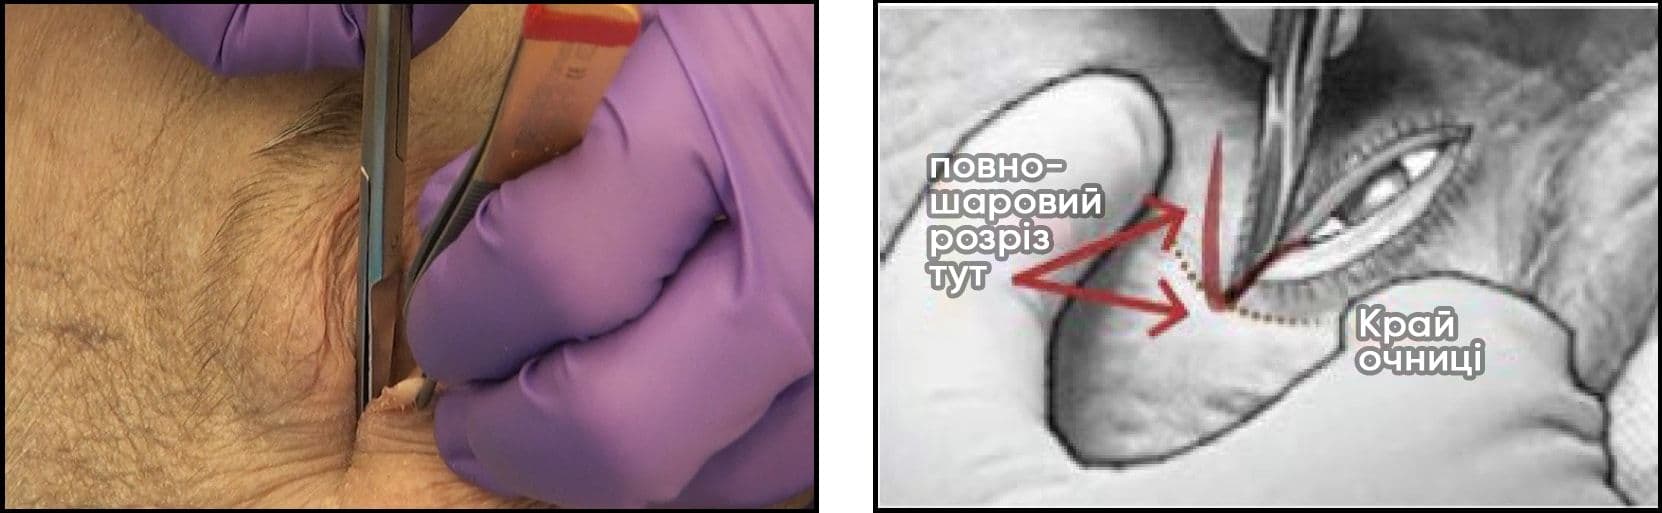

Латеральна кантотомія та нижній кантоліз

1. Якщо можливо, виконайте підшкірну ін’єкцію лідокаїну 2% з адреналіном у латеральний кант. Можуть виникнути труднощі із введенням ін’єкції в уже набряклу тканину.

2. Процедура є необов’язковою тільки за наявності належної місцевої анестезії. Прикладіть кровоспинний засіб або голкотримач горизонтально до латерального канта на 1 хвилину, щоб зменшити кровотечу.

3. Виконайте латеральну кантотомію.

Тупими ножицями розріжте латеральний кант на ВСЮ ТОВЩИНУ, на 1‒2 см до латерального кісткового краю очниці (кантотомія).

4. Виконайте нижній кантоліз:

• Зубчастим пінцетом міцно захопіть нижню повіку за край розрізаного канта (біля краю очниці) і відтягніть її в напрямку від ока.

• Тримаючи одне лезо ножиць за повікою (в кон’юнктивальному отворі), а інше — над шкірою, нахиліть ножиці до кута рота або носової раковини. Зробіть розріз НА ВСЮ ТОВЩИНУ нижньої повіки довжиною 1‒2 см. Це дозволить повністю витягнути нижню повіку. Можливо, перед розрізуванням вам вдасться промацати або «щипнути» нижню частину (нижній горбик) латеральної зв’язки кута очної щілини як «гітарну струну».

• У разі успішної процедури повіка має вільно рухатися і повністю відійти від очного яблука. Якщо повіка залишається в нормальному положенні, намацайте кінчиками ножиць залишки зв’язок і продовжуйте різати, доки повіка не буде вільно рухатися.

• Навіть при успішному вивільненні може не спостерігатися «струмінь крові».

5. Знову перевірте зір і внутрішньоочний тиск. Якщо внутрішньоочний тиск залишається підвищеним при поганому зорі і напруженому очному яблуці, то виконують верхній кантоліз, відокремлюючи верхню повіку від краю очниці. Також розгляньте можливість введення 500 мг ацетазоламіду внутрішньовенно.

Рисунок 33. Техніка виконання латеральної кантотомії та нижнього кантолізу.

Автор фотографії: CDR Eva Chou.

Рисунки A і B. Виконайте латеральну кантотомію. Тупими ножицями розріжте латеральний кант на 1‒2 см на всю товщину до кісткового краю очниці.

Зображення A

Зображення B

Зображення C і D. Виконайте нижній кантоліз: Зубчастим пінцетом захопіть нижню повіку за край розрізаного канта і відтягніть її в напрямку від ока. Тримаючи одне лезо ножиць за повікою, а інше — над шкірою, нахиліть ножиці до кута рота або носової раковини. Зробіть розріз НА ВСЮ ТОВЩИНУ повіки довжиною 1‒2 см. Можливо, перед розрізуванням вам вдасться промацати або «щипнути» нижню частину (нижній горбик) латеральної зв’язки кута очної щілини. У разі успішної процедури повіка має вільно рухатися і повністю відійти від очного яблука. Якщо повіка залишається в нормальному положенні, розріжте залишки зв’язок і продовжуйте різати, доки повіка не буде вільно рухатися. Навіть при успішному вивільненні може не спостерігатися «струмінь крові».

Зображення C

Зображення D